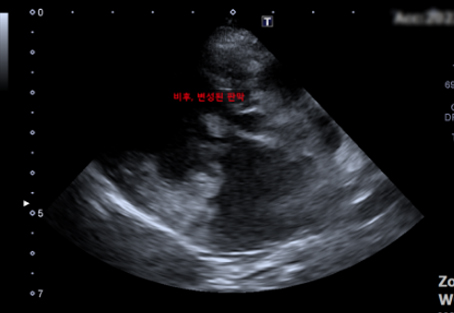

강아지는 사람보다 판막질환이 잘 발생하는 것으로 알려져 있습니다. 이첨판 폐쇄부전증은 이첨판 판막에 점액종성의 퇴행성 변성 및 비후가 일어나 판막의 폐쇄부전을 유발하는 질환입니다. 이러한 폐쇄부전으로 인해 판막이 제대로 닫히지 못해 역류가 발생하고, 결국 좌심방 내 혈액량을 증가시켜 울혈성 심부전까지 유발할 수 있는 질환입니다. 면밀한 검사를 통해 진행 단계를 평가하고, 그에 따른 내과적 관리가 중요합니다.

점액종성 승모판막 질환 (Myxomatous Mitral valve Disease, MMVD)

이첨판 폐쇄부전증 (Mitral valve Insufficiency, MVI)